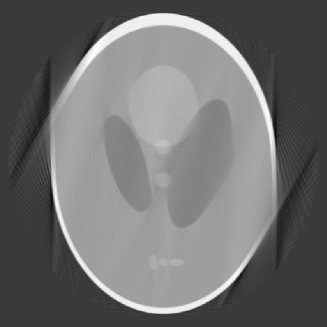

In our next example, we consider the case , which means that the data is limited to views with angles distributed over an arc of . The reconstruction with and is given in Figure 4.

In this image, artifacts and distortion are clearly visible and most prominent at two points on the edges of the images. The maximum of the conditional numbers in this case is merely 503, so that the matrices are in fact fairly well conditioned. This suggests that the distortion is likely caused by the choice of , which means that no polynomial preservation is kept.